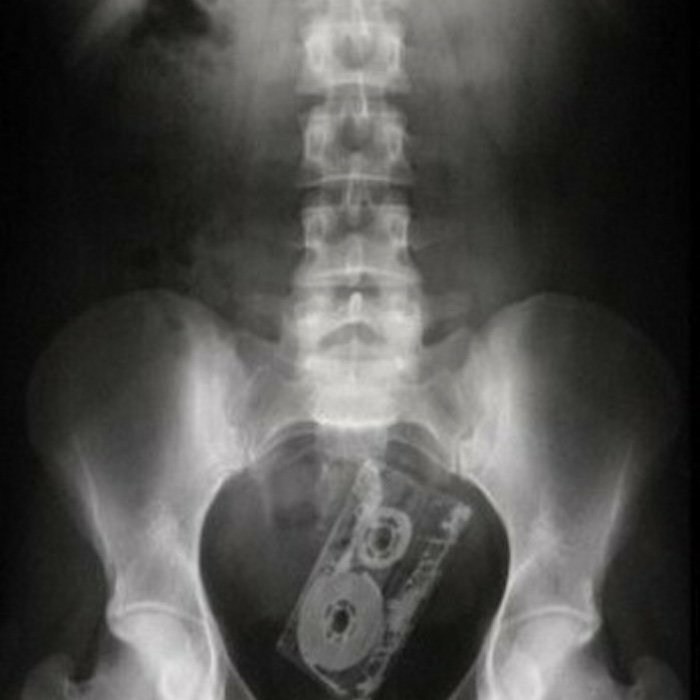

И смех, и грех. Секс – это удовольствие, но иногда он чреват травмами. Гости в студии рассказывают свои истории: в свое время они получили травмы поясницы и носа. А могут быть и более серьезные увечья…

Ведущие рассказывают, какие позы наиболее безопасны и не угрожают во время занятий сексом.